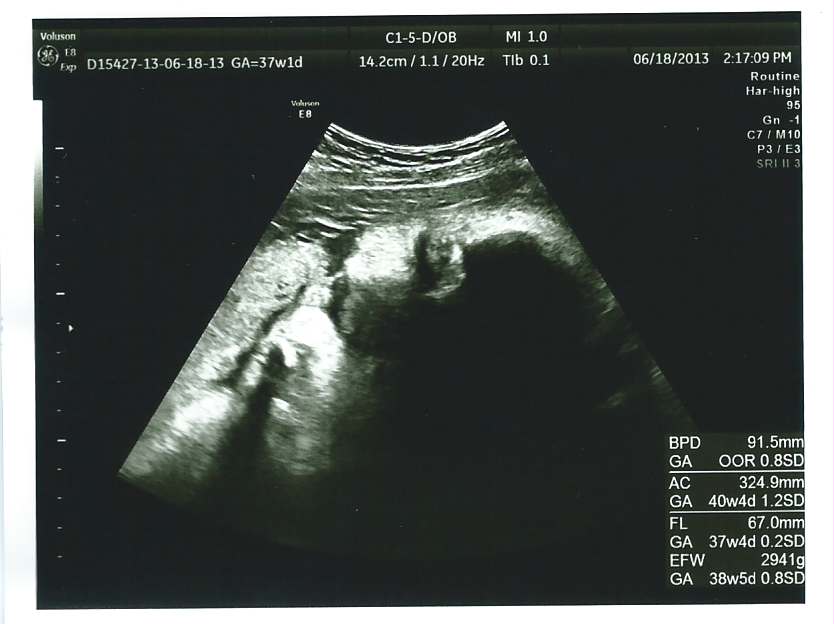

echo